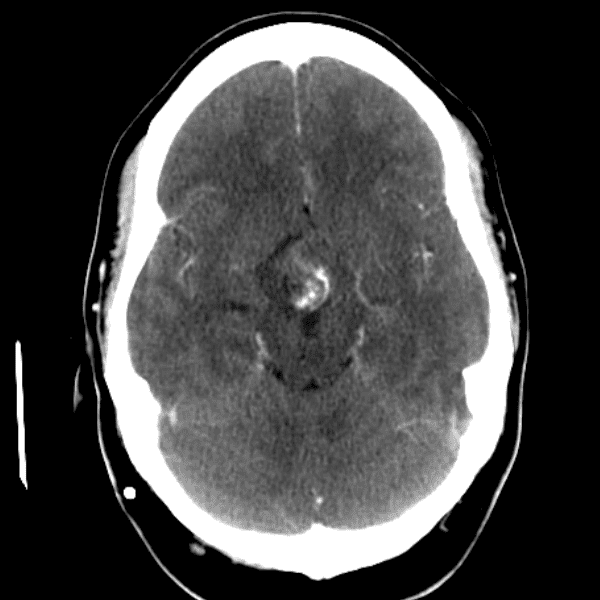

Classic Cases